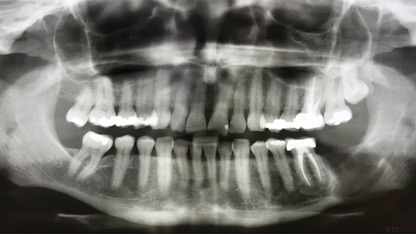

Rehabilitation of Both Failing Implants and Remaining Dentition with Implant Overdentures: A Case Report

Dabuleanu-fig-23-thumbnail alternate text for this image

Introduction A removable overdenture prosthesis is a practical rehabilitative alternative to a conventional complete denture as it is more comfortable, retentive, and satisfying for patients. It is a cost-effective alternative to a fixed implant-supported complete denture.1 Advancements in diagnostic, surgical and prosthetic technologies, combined with clinical research comparing different treatment outcomes, have resulted in an … Read more